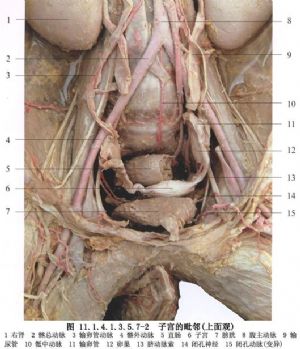

11.5 5.處理韌帶及子宮血管

根據病情切斷、縫扎圓韌帶、骨盆漏斗韌帶、子宮動靜脈,留結紮線牽引(圖11.1.4.1.3.5.7-14)。